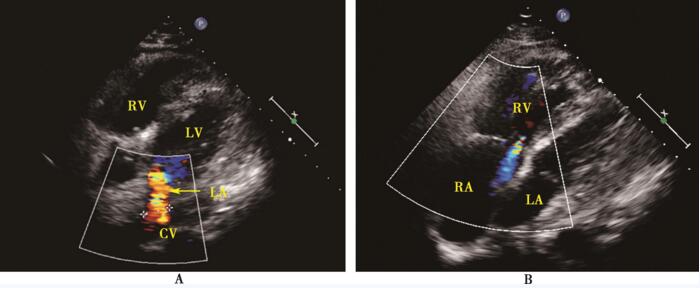

4月24日,行完全肺静脉异位引流矫治术,术中吻合肺静脉共汇入左心房顶切口,取心包补片4cm连续缝合修补房间隔缺损,结扎垂直静脉;三尖瓣行De Vega成形,环缩后瓣。术后动脉血气分析:PaO2 102mm Hg,血氧饱和度98%。术后超声心动图:右心房、右心室轻度扩大,左心房侧后壁与共同腔吻合口宽度1.6cm,房间隔中部可见强回声的补片、完整;彩色多普勒示吻合口血流通畅,心房水平未见异常分流,垂直静脉未见分流,三尖瓣未见明显反流(图42-2)。

图42-2 术后超声心动图

A:心尖近四腔切面彩色多普勒显示左心房后上方见一长管形共同腔与左心房吻合,吻合口内血流通畅; B:心尖旁四腔切面彩色多普勒显示右心房、右心室增大,少量三尖瓣反流,房间隔见强回声补片,房水平分流消失